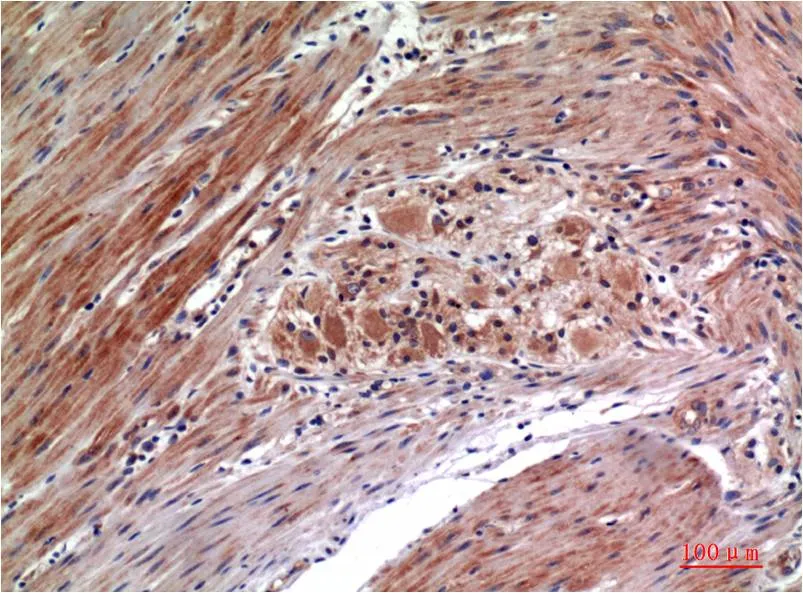

Desmin (4H1) Mouse Monoclonal Antibody

Cat: AMM00779

Size1:50μl Price1:$150

Size2:100μl Price2:$280

Size3:500μl Price3:$1200

Size2:100μl Price2:$280

Size3:500μl Price3:$1200